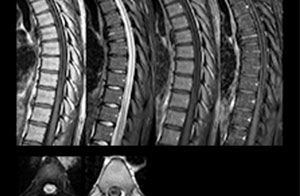

“We use mDIXON TSE extensively in our spine imaging in the emergency room,” says Dr. Karis. “It’s particularly nice in that it is very robust with regard to susceptibility type of problems that would come up with traditional spectral fat-saturated images; these problems are essentially eliminated with the mDIXON technique. In our ED environment it’s really nice to have the fat-free imaging that goes along with the mDIXON technique.

“For the thoracic and cervical spine routine non-contrast exam, for example, we perform one mDIXON T2 TSE sequence, which provides us with two outputs: the fat-and-water-together T2-weighted images, as well as the water-only sagittal T2-weighted images. And then we also perform an axial gradient echo exam.”